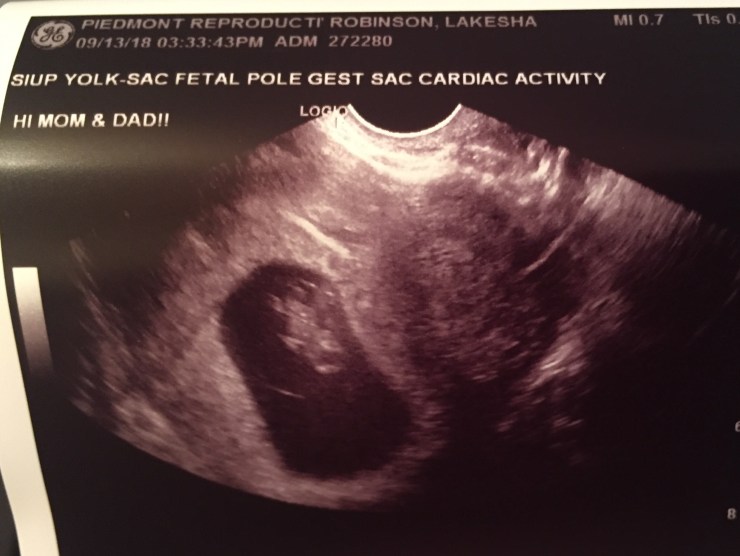

I was a nervous wreck all day. Anxious doesn’t begin to describe it. As soon as the ultrasound began and I saw our miracle baby appear on the screen, the tears just started flowing. I couldn’t stop crying and saying, “Thank You, Lord. THANK YOU.” Joseph immediately pulled out his phone and started recording what he was seeing on the screen. The baby’s heartbeat was 165 and you could see it just beating away. I am in awe and still am. It’s a moment I will never forget.

The next week I went back in for another ultrasound because I had more spotting, and I just wanted peace of mind knowing that the baby was OK. There’s a place off of HWY 9 behind Copper River Grill that does them for pretty cheap, and I went that day with a sick feeling thinking that something was wrong and that I wouldn’t be able to see my baby. I was trying to brace myself for the worst. Yet, as soon as the image appeared on the screen, I was once again filled with wonder. Our little baby was alive and well with a strong heartbeat. Everything was OK. The technician there asked why I had come in that day and I shared with her the story of how the baby came to be and about Carter. She then shared that she had lost her brother to suicide years ago, and she understood how hard that kind of loss is on a family. I think that Lord allowed me to go to that appt. just to share Carter’s story with her and to relate to her pain on some level. I really do believe that. I haven’t had any spotting whatsoever since that day.

I’m starting to sport a little baby bump, so I can’t keep the secret any longer. We are telling everyone this afternoon. Joseph wanted to me share the news on the blog so you guys will be hearing it first as followers before I share the blog on social media later on today. We are so happy that we have something exciting to share. We told Caroline a few weeks ago, and she was stunned at first and didn’t know what to say. She wants the baby to be a girl, but she has said that little boys are the sweetest around 3 years old, so I think she is good either way. She will be an amazing big sister…she’s always been so nurturing and loving with babies and littles at our church. She was able to go with us to our 12 week ultrasound with Dr. Toler this week and lit up when she saw the baby moving around like crazy and saw the heartbeat on the screen.

I have been referred to Maternal Fetal Medicine for an appt. with a genetic counselor and a more in-depth ultrasound this upcoming week. I don’t see a real need for the genetic counseling, because it won’t change anything. This baby is ours and we’re keeping it regardless of what a test may show, but if something is wrong and there’s things we can do to help our baby’s chances in utero, then of course we want to do that. Dr. Toler says everything looks great so far, so this appt. is more like something we have to just “check off” since they are routinely scheduled for women like me who are ‘of advanced maternal age”, lol. The good part is that we get some more cool ultrasounds of our baby, and we relish those opportunities!